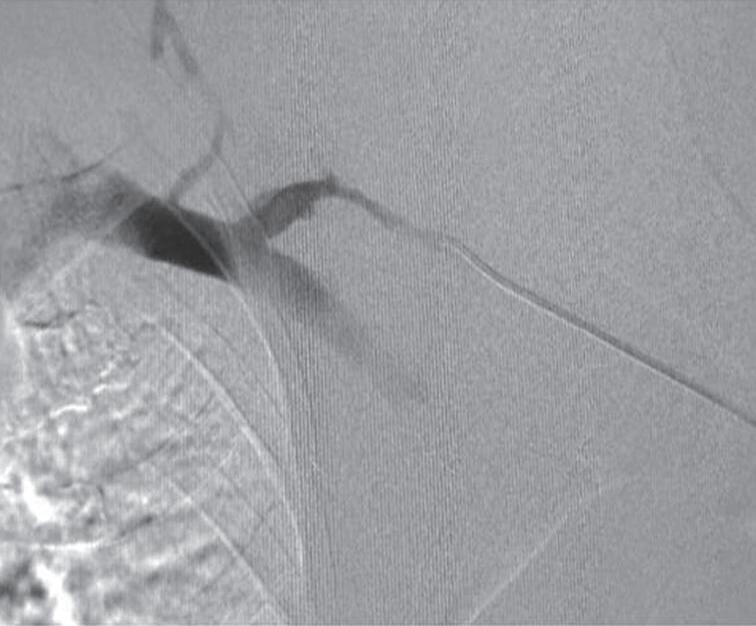

As fístulas arteriovenosas (FAV) nativas funcionais são consideradas os acessos vasculares de escolha para a realização de hemodiálise (HD) em decorrência de menores custos, melhores taxas de perviedade, menor morbidade e menores taxas de mortalidade quando comparadas com outras modalidades de acesso vascular.1-5 Entretanto, após a confecção de uma FAV, é necessário um período de algumas semanas para que o acesso possa ser utilizado. Esse tempo é conhecido como período de maturação do acesso. Apesar dos resultados superiores das FAV, 23% a 46% desses acessos apresentam problemas para atingir um diâmetro e fluxo adequado para sustentar diálise efetiva.5-8 Esses problemas são descritos na literatura médica como falha de maturação do acesso.9 Recentemente, alguns autores têm recomendado o salvamento de uma FAV não maturada por meio de intervenções endovasculares. Essas intervenções são conhecidas como maturação assistida por balão (BAM).10-12 O objetivo deste capítulo é descrever as técnicas e os resultados dos procedimentos endovasculares para promover a maturação das FAV em falência.

Figura 26.13 (A a F) Aspecto pré‑ e pós‑maturação assistida por balão superdimensionado (oBAM; do in glês, oversized balloon assisted maturation) Fístulas arteriovenosas braquiocefálica com múltiplas esteno ses (setas vermelhas), estenose justa‑anastomose (seta amarela) e importante circulação colateral (setas pretas) (A e B) Arco venoso cefálico (C) Aspecto pós‑oBAM com balões de alta pressão 6 e 8mm (D a F)

Fonte: arquivo pessoal dos autores

pacientes foram submetidos à eco-Doppler colorido pós-operatório para a análise do diâmetro do vaso, a mensuração do volume de fluxo e a posterior canulação da FAV nos casos em que a intervenção foi bem-sucedida. Percebemos sucesso

técnico e clínico em 91% dos pacientes (Tabela 26.1). As taxas de perviedade primária em 3, 6 e 12 meses foram de 87,3%, 66,2% e 50,7%, respectivamente, enquanto as taxas de patência secundária se mostraram de 100% em três